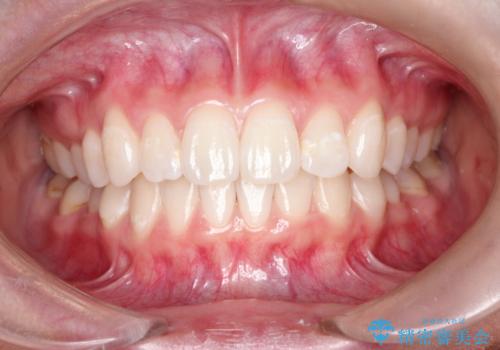

前歯の突出、深い噛み合わせ、ガタつきをマウスピース矯正(インビザライン)で治療した症例

このケースでは非抜歯にて奥歯を後方に移動させる事で前歯の突出を改善するスペースを作り出していますが、これはマウスピースと顎間ゴムの併用によるもので、患者様のご協力の賜物と言えます。

深い噛み合わせについてはシミュレーション上の結果と、予期される実際の歯の移動量とを考慮し、特殊なセットアップを行う事で望ましい結果を得ることができました。

治療途中でリファインメントという追加のマウスピースを製作する手順を行っていますが、その際に上下の正中を合わせたいとの要望があったため、追加シミュレーションの際に追加でセットアップを施しましたが、無事、上下の正中もご要望通りに改善しています。

使用した装置はマウスピースと顎間ゴムのみです。ワイヤーやマイクロインプラントなど補助装置の使用はありません。